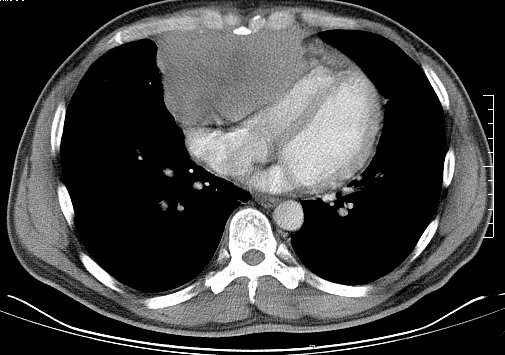

男   40   反复腹痛入院行彩超检查示胸骨右缘4、5肋间不均质回声团

淋巴瘤:前纵隔可见多组肿大的淋巴结,部分融合,有液化坏死

上区却那么有点象占位,胸腺瘤不太象,一点强化也没有,淋巴瘤气管前上腔静后却很干净,下区也点象纵隔积血征,

纵隔恶性肿瘤,考虑生殖细胞肿瘤可能性大。